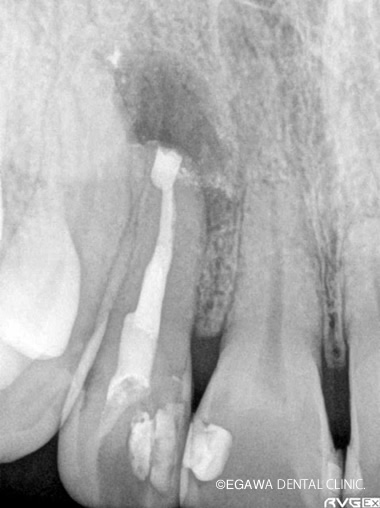

術前:レントゲン

術後:レントゲン

直接覆髄で歯髄を残せました(凹凸部分がMTAの箇所)

不幸にして歯髄治療を行わなければいけない場合、ファーストチョイスで直接覆髄を行いますが、直接覆髄でもダメなケースは根管治療を行います。まずは根管治療を行い、もし治らない場合は、根管治療は何度も続けるものではありません。その場合、後述でご紹介している歯根端切除術などの外科的な根管治療に移行します。その際、CTによる精密な診査・診断が必要となります。